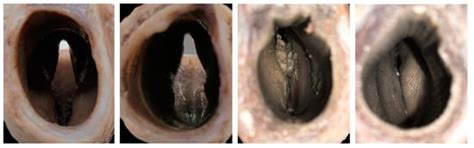

Anatomy and Pathology of the Texel Sheep Larynx